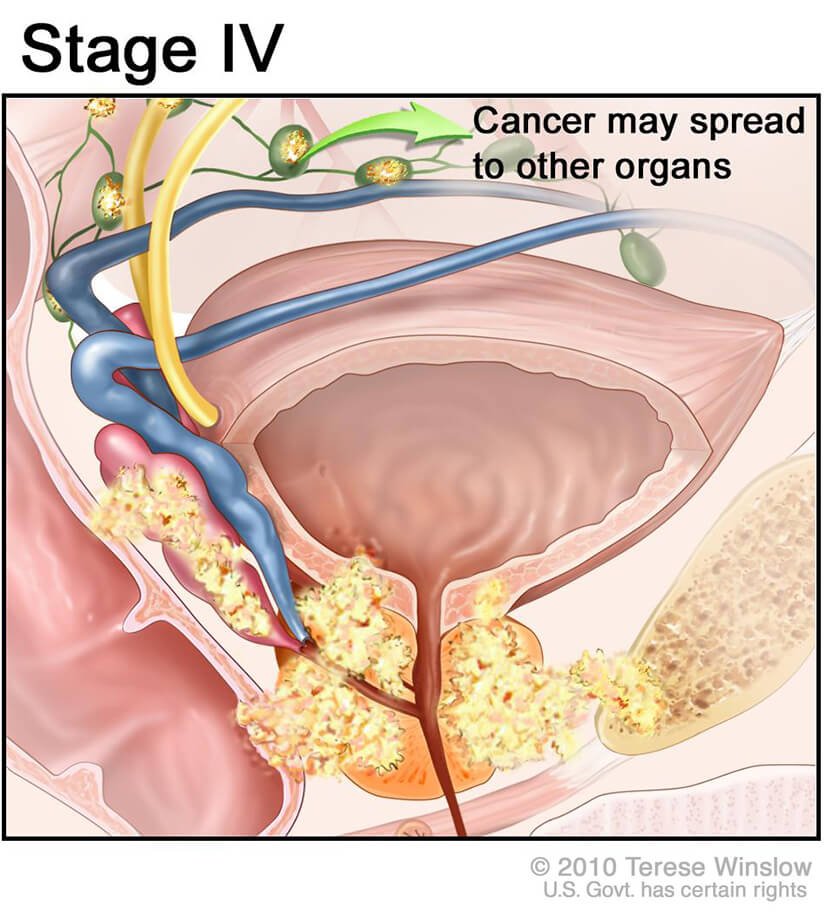

The Spread of Prostate Cancer – Prostate Cancer Research Centre